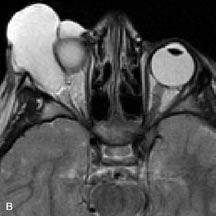

MRI is also effective in imaging orbital tumors of mesenchymal origin, such as rhabdomyosarcoma, particularly in the assessment of extension into the anterior and middle cranial fossae (Fig. 17).37 The lack of any pathognomonic radiologic features necessitates rapid orbital biopsy when rhabdomyosarcoma is suspected.

Fig. 17. A. T1- and (B) T2-weighted MR scans demonstrate a preseptal and extraconal mass displacing the globe medially. The mass is slightly hyperintense on the T1-weighted scan and very hyperintense on the T2-weighted scan owing to the high extracellular water content of the neoplasm. The lesion abuts the globe and appears to infiltrate the lateral rectus muscle (arrow). C and D. Postcontrast fat-suppressed T1-weighted scans demonstrate intense enhancement of the highly infiltrative lesion that is invading the lateral rectus, superior rectus, and levator palpebrac superioris muscle (double arrows).